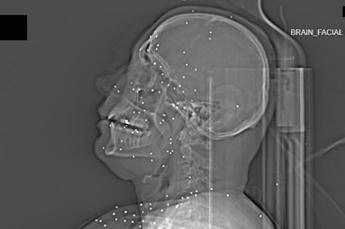

(Adnkronos) – Il Guardian, quotidiano britannico da anni impegnato nel documentare violazioni dei diritti umani, ha pubblicato un’inchiesta che aggiunge un tassello crudo e difficilmente contestabile alla comprensione della repressione delle proteste in Iran. Non si tratta di testimonianze verbali, non di racconti filtrati dalla distanza o dalla propaganda, ma di immagini mediche: radiografie e Tac. Fotografie in scala di grigi che mostrano, letteralmente, la violenza impressa nei corpi.

Il volto di Anahita – nome di fantasia, poco più che ventenne – appare come un cielo notturno attraversato da punti luminosi. Piccole sfere metalliche, da 2 a 5 millimetri, disseminate sul viso, nelle orbite oculari, persino nella massa scura del cervello. Sono proiettili “birdshot”, pallini da caccia sparati da un fucile a pompa. A distanza ravvicinata, spiegano gli esperti, non sono affatto “meno letali”: possono frantumare ossa, devastare tessuti molli, perforare facilmente un bulbo oculare. Anahita ha perso almeno un occhio, forse entrambi.

Quell’immagine non è un caso isolato. Fa parte di oltre 75 set di esami diagnostici provenienti da un singolo ospedale di una grande città iraniana, raccolti nel corso di una sola serata, durante la stretta repressiva di gennaio. Una concentrazione temporale che, già di per sé, racconta una dinamica da “mass casualty”, evento con numerose vittime simultanee, tipico degli scenari di guerra o dei grandi disastri.

Le scansioni mostrano ferite che i medici definiscono “catastrofiche”. Vahid – altro nome modificato – presenta un proiettile di grosso calibro conficcato nel collo. La trachea è spinta lateralmente, il sangue si accumula, i tessuti gonfi e danneggiati comprimono le strutture vitali. In un altro caso, un uomo di mezza età ha un proiettile sospeso nel cervello, accompagnato da una bolla di gas intracranica: segno di trauma devastante, al quale verosimilmente non si può sopravvivere. Due giovani uomini mostrano pallottole ad alto calibro alloggiate accanto alla colonna vertebrale. Una giovane donna presenta un proiettile deformato che sembra aver attraversato la gabbia toracica, lesionato il polmone e arrestato la sua corsa vicino alla spina dorsale.

Le radiografie raccontano questa brutalità in modo quasi didascalico. Il torace di Ali – anche qui, nome di fantasia – contiene oltre 174 pallini metallici concentrati nella cavità destra. Il polmone parzialmente collassato, circondato da sangue e gas. Secondo gli esperti consultati, anche con un intervento chirurgico immediato e massiccio, il rischio di morte rimane altissimo.

Ma non è solo la gravità delle ferite a colpire. Caso dopo caso, le immagini mostrano corpi colpiti al volto, al torace, ai genitali. Ventinove pazienti risultano feriti al viso da birdshot. Almeno nove presentano lesioni nell’area genitale o pelvica, provocate sia da pallini sia, in alcuni casi, da fucili ad alto calibro.